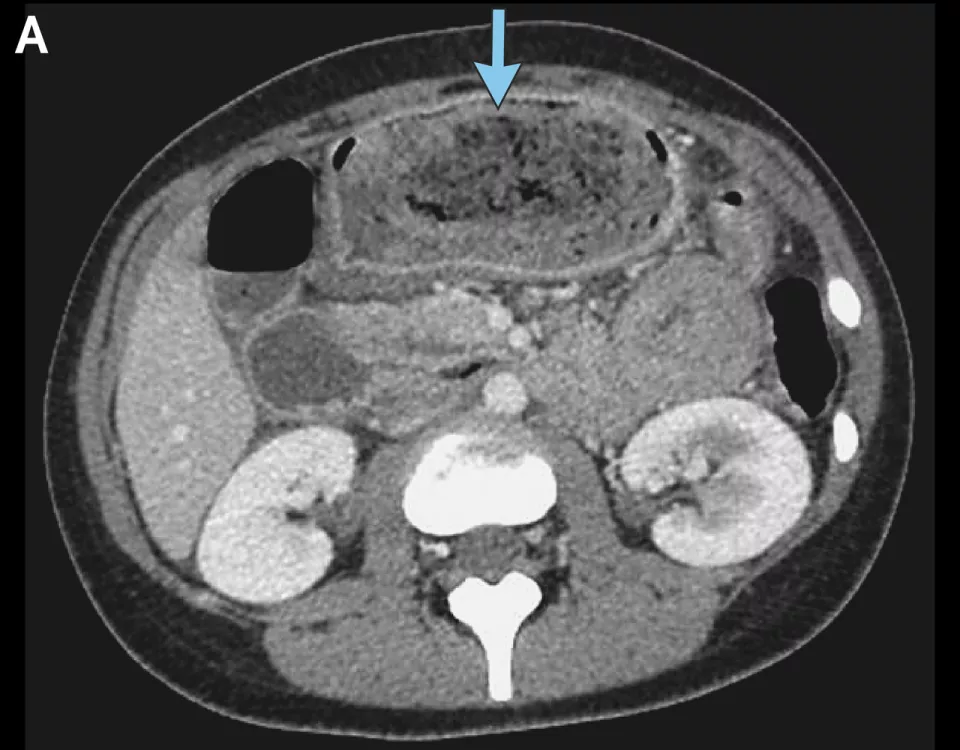

左滑查看更多图片:胃石示意图、手术中看到的毛发性胃石、CT检查中的胃石 | 参考文献[1]

胃石形成,主要是因为难消化和排不出。难消化的,包括柿子、山楂、某些药物和毛发等异物。排不出是指胃肠功能不足,难以把胃内物质碾碎推到肠道里,原因可能在胃肠、糖尿病、自主神经病变或者影响胃动力的药物(如三环类抗抑郁药,以及本患者使用的司美格鲁肽、缓解腰背痛的阿片类强效镇痛药)。

胃石形成后,可以引起腹痛、恶心及呕吐的症状,如果出现溃疡、出血、梗阻等并发症,还可能有血便、呕血等表现。有时,胃石患者没有症状,是做胃镜检查时偶然发现的。